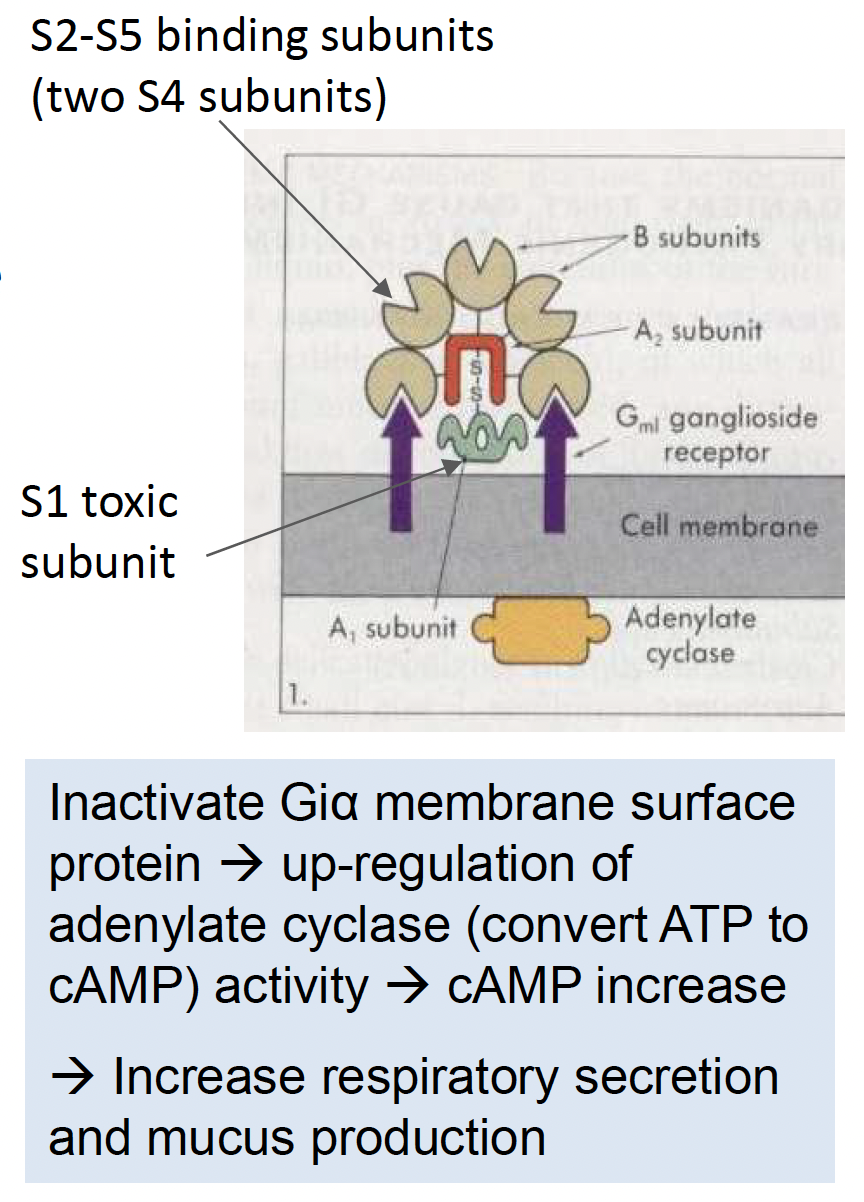

- Pertussis toxin

- AB toxin

- A: S1

- B: S2-S5

- AB toxin

| Pertussis toxin | cAMP↑ | Bordetella pertussis (百日咳) |